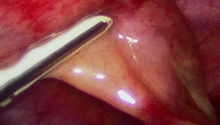

3点“狗耳”矫正